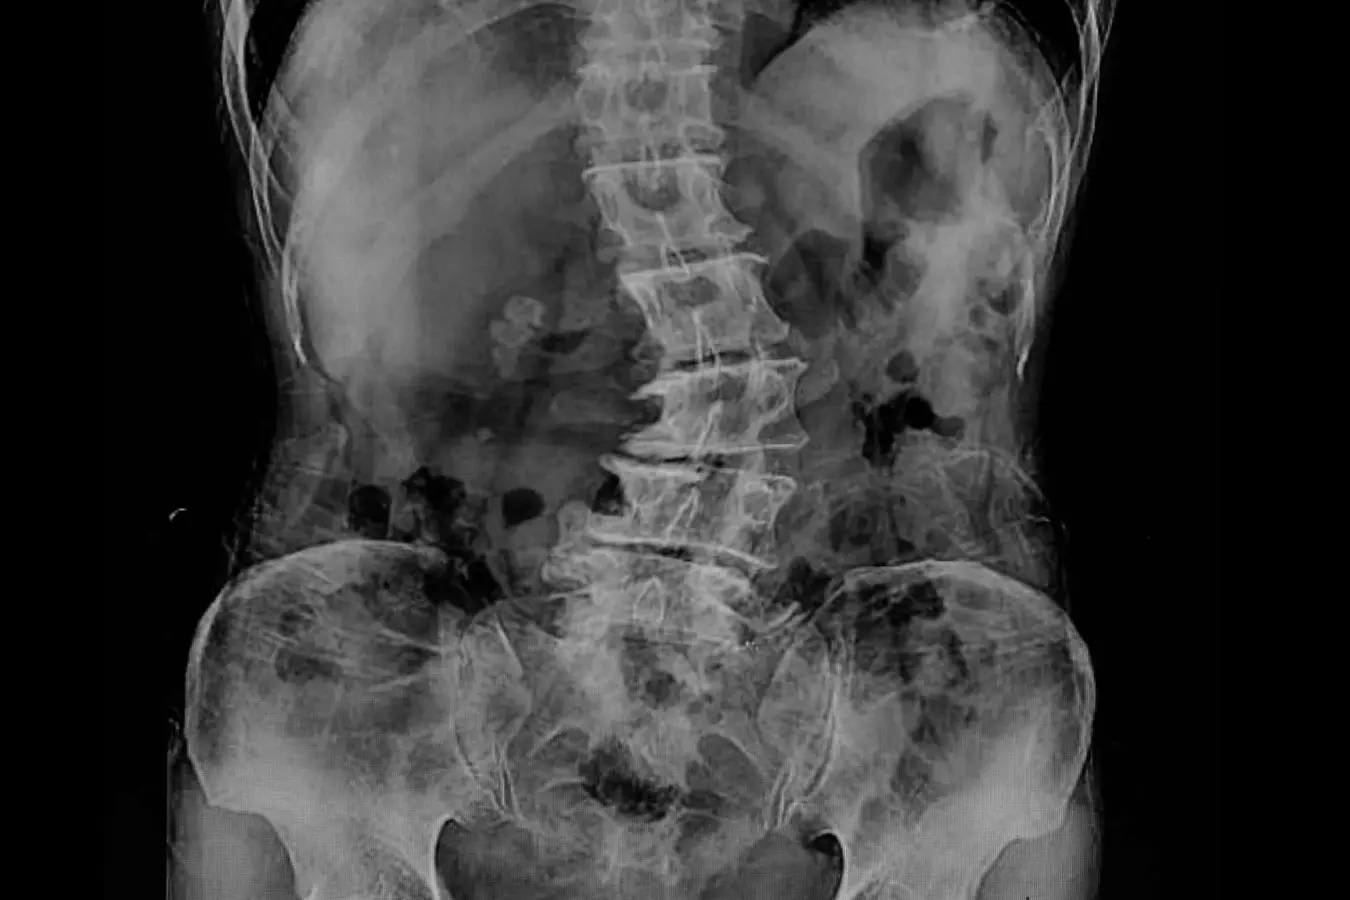

«La radiología digital dinámica tiene utilidad en los estudios ortopédicos en los que se aprecia una imagen radiográfica del movimiento de las articulaciones como la muñeca, el hombro o la rodilla. También tiene gran utilidad para estudiar la columna en flexión y extensión. Nos ofrece una visión muy completa del movimiento de la articulación», explica el Dr. Martínez de Vega, que también cree que esta nueva tecnología tiene otro punto fuerte en los estudios de función pulmonar: «Puede tomar imágenes de dos o tres respiraciones completas del paciente y mostrarnos una imagen en movimiento en el que se visualiza con claridad cómo se llenan y vacían los pulmones y el movimiento del diafragma. Se aprecia si existen adherencias pleurales o si hay zonas que no ventilan correctamente. A la información visual del cineloop (imágenes en secuencia), se pueden añadir mapas de ventilación y del movimiento realizados gracias a softwares avanzados específicos de la estación de trabajo, que analizan las diferentes densidades del pulmón y ofrecen al radiólogo datos cuantificables de función pulmonar». Según el Dr. Martínez de Vega, esta información es muy útil en las Unidades de Cuidados Intensivos en los que ayudará a valorar más adecuadamente la evolución de los pacientes desde el punto de vista cardiopulmonar. Otra gran ventaja de este equipo es que es portátil, lo que permite realizar los estudios a pie de cama de los pacientes sin necesidad de desplazarlos.